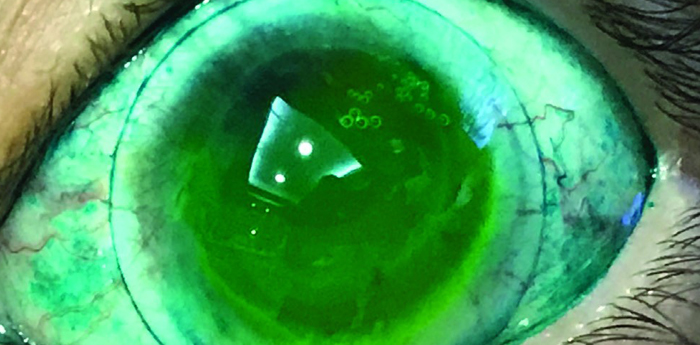

Se trata de una paciente de 28 años de edad quien acude a consulta de optometría por presentar disminución de su agudeza visual e incomodidad con sus lentes de contacto habituales. Al hacer la anamnesis informa que le realizaron cirugía Lasik a los 15 años de edad....